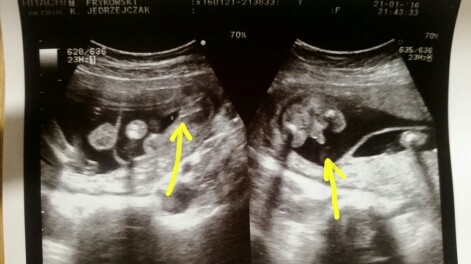

2016-01-21 23.18.40.jpg

No to u mnie parka ;) chłopak 270g dziewczynka 260g. Dzis ułożone posladkowo - ale to jeszcze maluchy wiec wszystko sie moze zmienic. Szyjka długa 4.2 cm i zamknięta wiec spokój ogarnął moja duszę - idziemy do przodu :D

• 2016-01-21 23.18.40.jpg

32,7 KB · Wyświetleń: 325